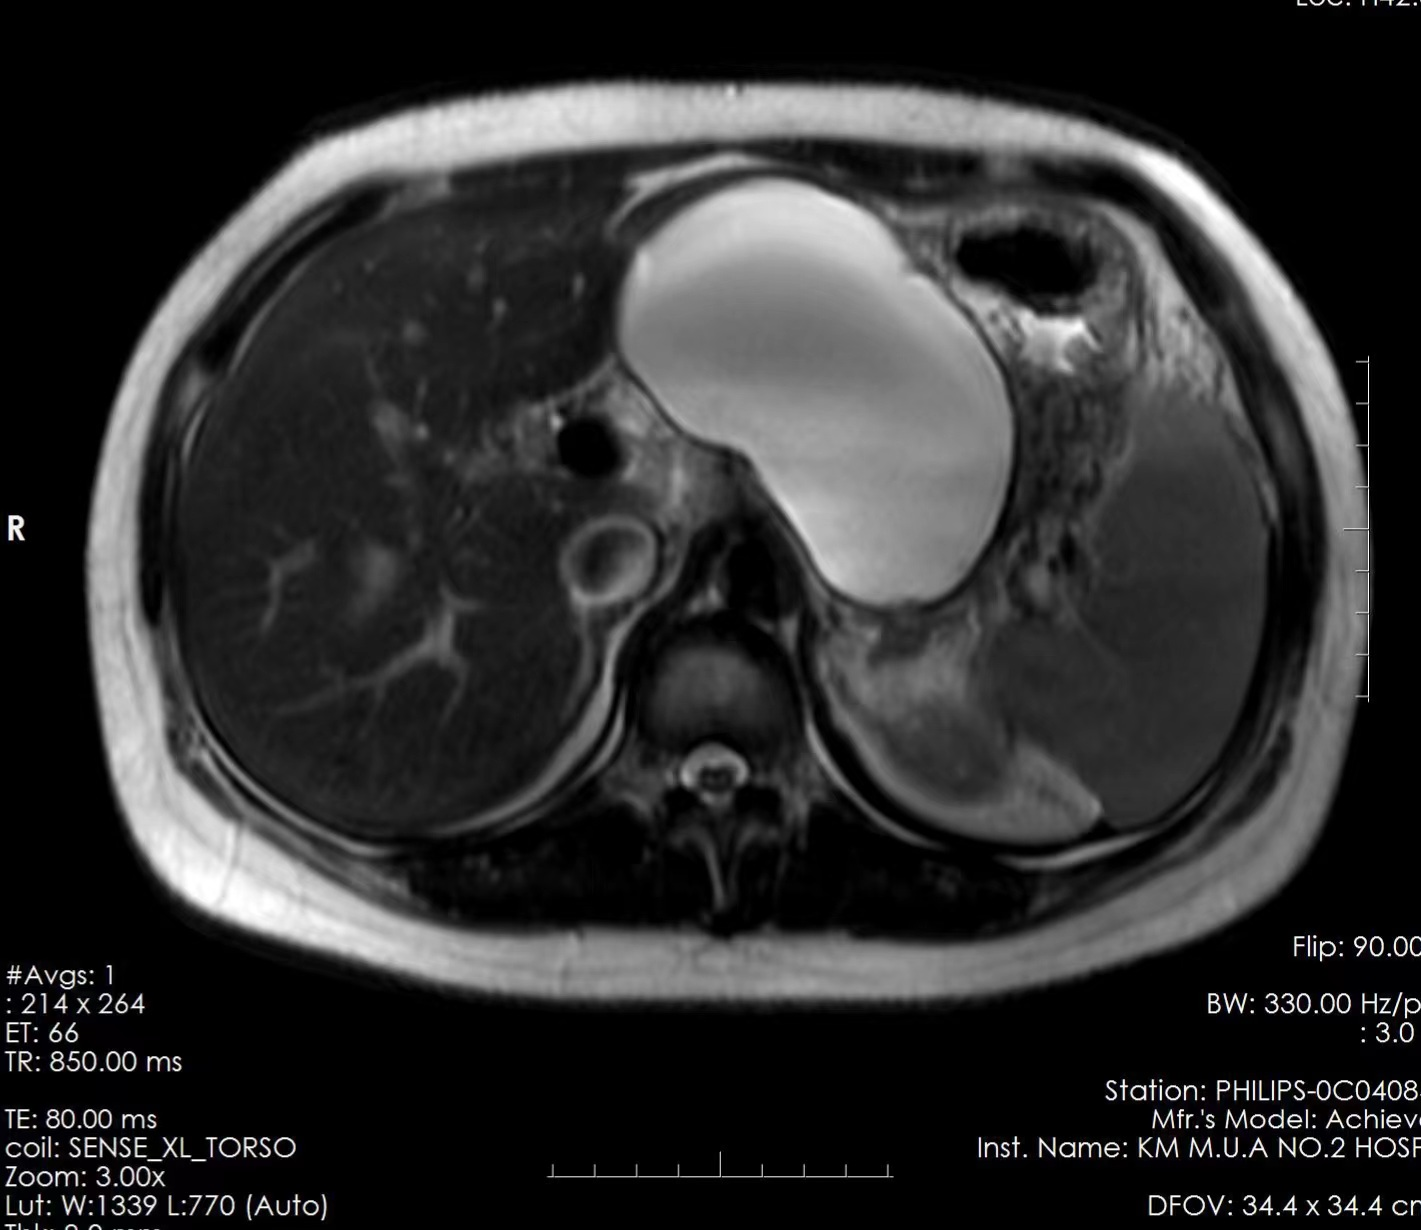

患者,30岁,女性,约三个月前因急性重症胰腺炎转至我院消化内科一病区治疗,经过李俊主任团队的精心治疗,患者症状得到缓解,正常进食,顺利出院。可是,没高兴多久,患者又开始出现腹胀的症状。复查CT和MRI提示胰腺假性囊肿,大小约11cmX7cm,于6月9日再次入住消化内科一病区,并且胃镜检查出现胃底、胃体静脉曲张(区域性门脉高压,考虑囊肿压迫所致),随时有静脉曲张破裂出血风险。为有效缓解患者胰腺假性囊肿引起的症状及并发症,经消化内科李俊主任团队讨论,并取得患者及家属同意后,建议患者实施EUS下较前沿的技术:EUS引导下胰腺假性囊肿穿刺引流术。

2023年6月13日下午,在麻醉手术科团队合作下,李俊主任指导帮助,由刘国彬副主任医师为患者实施EUS引导下胰腺假性囊肿穿刺引流手术。在胃内EUS引导下精确定位囊肿后,顺利将引流管经胃壁置入囊肿内,将大量棕红色囊液引出,手术顺利,手术操作约20分钟,术后患者无不适。三天后复查腹部超声囊肿明显缩小,患者腹胀明显缓解,顺利出院。出院后电话随访患者无不适,嘱患者一月后入院复查拔管。